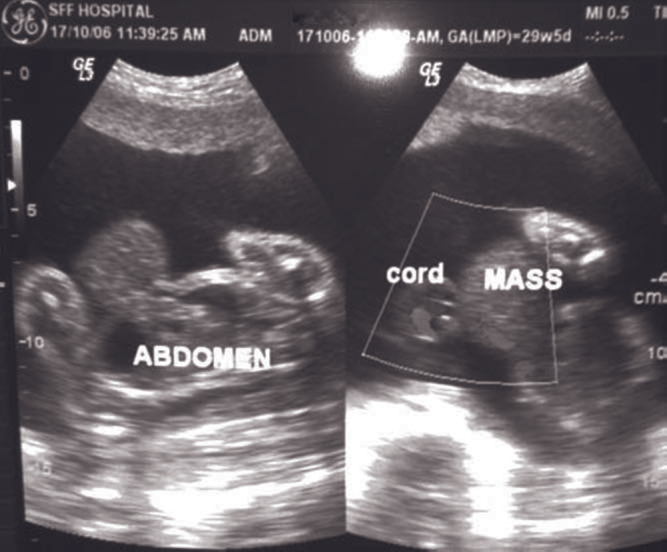

Fig. 2.

Ultrasonography and doppler scan showing umbilical cord attached to the apex of the herniated mass.